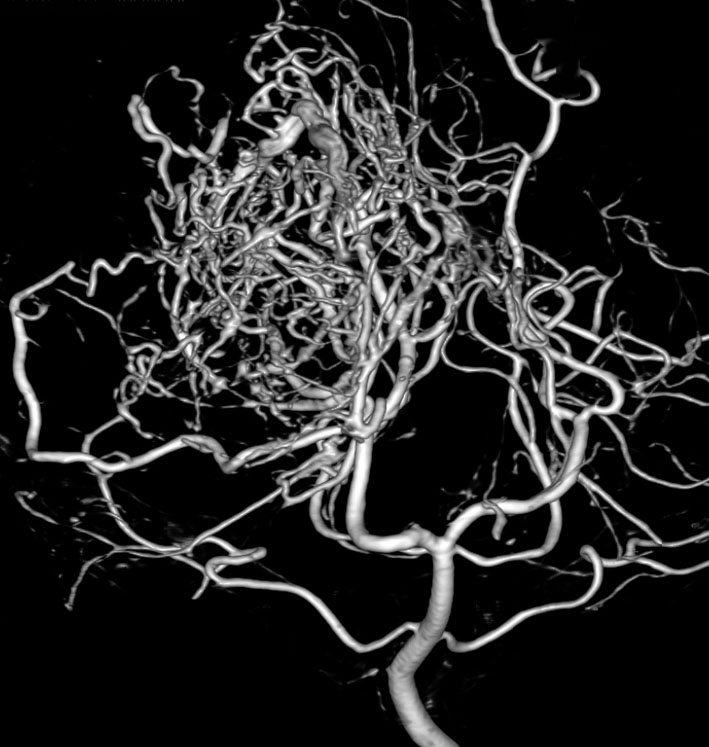

テント上 退形成性上衣腫 グレード3:EPN-ST-RELA negative

膠芽腫を思わせるような,腫瘍内部の壊死,のう胞形成,出血があります。高度の血管増生と動静脈シャントがあり,早期腫瘍静脈描出 early venous fillingがみられます。10代のおそらく右側脳室三角部辺りから発生した退形成性上衣腫です。激しい出血がありましたが全摘出 gross total removal しました。リスクをかえりみない手術も必要です。画像所見も病理組織像も超悪性腫瘍なのですが,治る可能性があるタイプです。